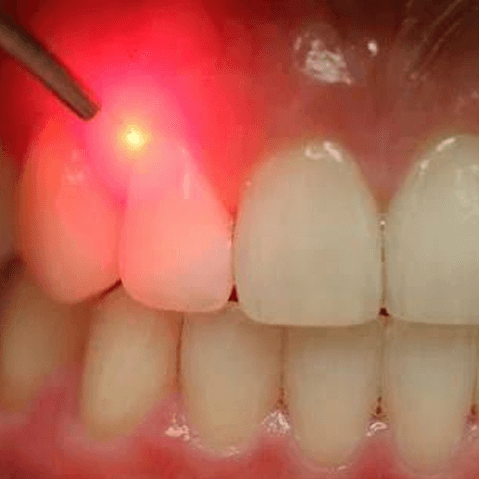

Say Goodbye to Bleeding Gums: Best Gum Disease Treatment in Karachi at Altamash Dental Clinic

A healthy smile is what you think of when you imagine it, maybe flashing shiny white teeth. But there is one super crucial area of oral health which is easily overlooked, your gums. We do care about gum health at Altamash Dental Clinic since gums are the gateways to a healthy mouth. Whether you [...]

Altamash Dental Clinic: Your Trusted Partner for the Best Gum Disease Treatment in Karachi

Oral health has a lot to do with your well-being, and everything starts with healthy gums. Gum disease, though not often considered by many, can become serious if you fail to seek treatment when it is present in your oral cavity. So, whether you need early-stage gum disease treatment or want to learn ways to [...]

Comprehensive Guide to Gum Health and Periodontal Disease Treatment

Healthy gums are crucial for overall health, as gum disease can lead to serious complications like tooth loss and systemic issues. Regular dental check-ups, proper oral hygiene, and early treatment of any gum issues are key to maintaining a healthy smile. Maintaining Healthy Gums: Essential Tips Maintaining good oral hygiene is vital for [...]